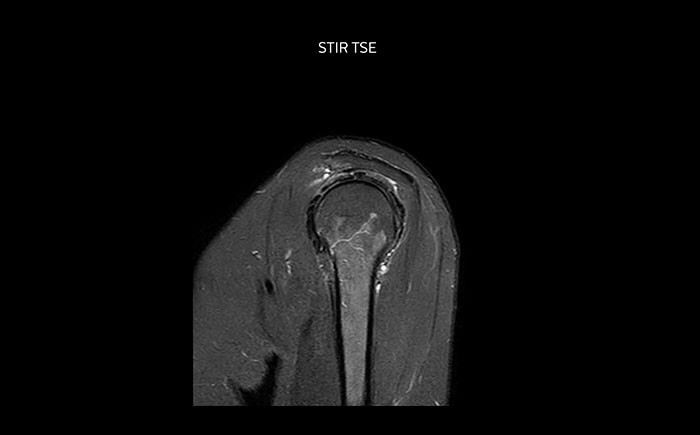

Shoulder MRI with high quality, large coverage

The Prodiva shoulder coil is very flexible and has large coverage, which makes good positioning easier, and that contributes to the superb image quality and high SNR that we get in our shoulder exams.

Scan time 2:55 min, FOV 160 mm,

acq voxels 0.55 x 0.83 x 3.0 mm.

Scan time 4:19 min, FOV 160 mm,

acq voxels 0.55 x 0.80 x 3.0 mm.

Scan time 2:50 min, FOV 160 mm,

acq voxels 0.70 x 0.99 x 3.0 mm.

Shoulder MRI with high quality, STIR TSE